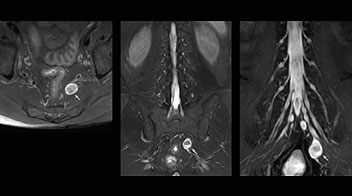

Northern Fukushima Medical Center (NFMC) Imaging Center uses the 3D NerveVIEW sequence for performing MR neurography, particularly in patients with pain and weakness in the lower limb. “It is included in about 20% of the approximately 150 lumbar spine MRI exams each month at NFMC, and can help us to determine if structures are impinging on the nerves,” says Hajime Tanji, RT, MRI technologist at NFMC.

“In such case, we would then browse through axial T2-weighted MR images slice by slice and mentally reconstruct the actual situation based on both radiculography and MRI. Fortunately, NerveVIEW can now very well show nerve courses and presence of nerve compression or edema in one single image series.” “We have often seen NerveVIEW directly depict details of the nerve compression that were not observed by radiculography. Therefore, we think that with NerveVIEW we can reduce the number of invasive examinations, especially for some patients with lumbar plexus symptoms.”

“The intra-luminal signal of veins, especially around the intervertebral space, can be suppressed well with NerveVIEW. As a result, we can easily observe the detailed nerve structure around the posterior ganglion,” he says. “This is why we use 3D NerveVIEW for intraforaminal stenosis and extraforaminal stenosis/herniation (lateral disc herniation). On the other hand, if herniation is suspected to exist inside the dorsal root ganglion (DRG), balanced TFE or ProSet-FFE is applied. NerveVIEW is not suitable for evaluating the median type of herniation.” The SE-EPI DWI-based method for MR neurography works well for large FOV exams like whole-body MRI, but focal examination of nerves is often limited by the attainable spatial resolution (both inplane and slice direction) and geometric distortion. “3D NerveVIEW achieves higher in-plane resolution – close to our other routine spine sequences – and the source images can be used instead of adding a fat-suppressed T2-weighted sequence,” Tanji says.

According to Tanji, methods such as ProSet FFE, STIR or 3D VISTA are anatomically nonselective because background signals, for instance from blood vessels, often interfere with nerves, which hampers evaluation of details, especially at the peripheral side of the nerves.

“For both brachial and lumbar plexus, we are currently using a 230 mm FOV and voxels of about 1 x 1 x 2 mm acquired (1 x 1 x 1 mm reconstructed). This provides us a good representation of the nerves, even though this FOV is relatively small. Regarding the inplane resolution, we hope to be able to bring that down to 0.7 mm, similar to our typical 2D multislice T2W images,” says Tanji.